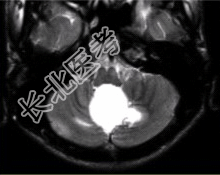

- [材料题] 男性,20岁。恶心、呕吐3d,剧烈头痛加重1d入院。MRI显示小脑下蚓部长T₁、长T₂信号影,病变可见结节状明显强化,如下图。